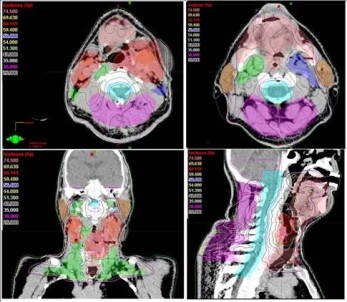

Son yıllarda yapay zeka uygulamalarının kanser alanında kullanılmasına yönelik araştırmalarda artış olduğunu ifade eden Prof. Dr. Yavuz, “Tümör ve çevredeki normal dokuların üç boyutlu olarak sınırlarının çizildiği bu süreç, bir hastanın tümör bölgesine ne kadar radyasyon alacağını ve ışının en uygun nasıl odaklanacağını belirler. Özellikle ABD’nin Ulusal Sağlık Enstitüsünce desteklenen önemli bir araştırma projesinde "Yapay Zeka’ kullanarak yüksek riskli tümör hedef hacimlerinin sınırlarının 3 boyutlu olarak belirlenmesi için her bir görüntüleme film kesitinde tümör ve normal doku sınırlarının tek tek çizilmesi (konturlama) işlemlerini otomatikleştirmek için yeni bir yöntem geliştirildi” dedi.

Bu çalışmanın sadece yüksek riskli tümör hacimlerinin ’Yapay Zeka’ ile otomatik bir şekilde ve çok yüksek doğrulukta belirlenmesine yönelik olduğunu dile getiren Prof. Dr. Yavuz, "Bir sonraki aşamada, eldeki tüm veriler birleştirilerek, orta ve düşük riskli tümör bölgelerinin de otomatik ve en doğru bir şekilde belirlenmesi mümkün olabileceği gibi, hastaya özgü en uygun radyoterapi veya kemoterapiyi de ayarlamak adına çeşitli genetik mutasyonlara ait bilgiler de bu yapay zeka uygulamasına entegre edilebilecektir. Bu şekilde, kanser tedavisi sonuçlarında başarı oranlarının artması da kaçınılmazdır. Yöntemin çok önemli bir avantajı da bizlere sunduğu yüksek hız ve verimliliktir. Normalde, örneğin bir baş boyun kanserinde, hedeflenen hacimleri belirlemek bir hekimin 1-4 saatini alır. Yapay Zeka kullanan özel bilgisayar sistemi ile hem bir dakikadan kısa bir sürede hedef hacimler belirlenebilmekte, hem de hekimden hekime değişebilen hata payları ihtimali tümüyle ortadan kalkmaktadır. Bu yöntem, özellikle, hedef hacim belirleme alanında tecrübeli uzman sayısının daha az olduğu düşük ve orta gelir düzeyindeki ülkelerde çok büyük bir kolaylık sağlayacaktır, ancak bu yöntemin ABD gibi gelişmiş ülkelerde de kanser tedavilerindeki yararlılık ve verimliliği çok artıracağı açıktır" şeklinde konuştu.